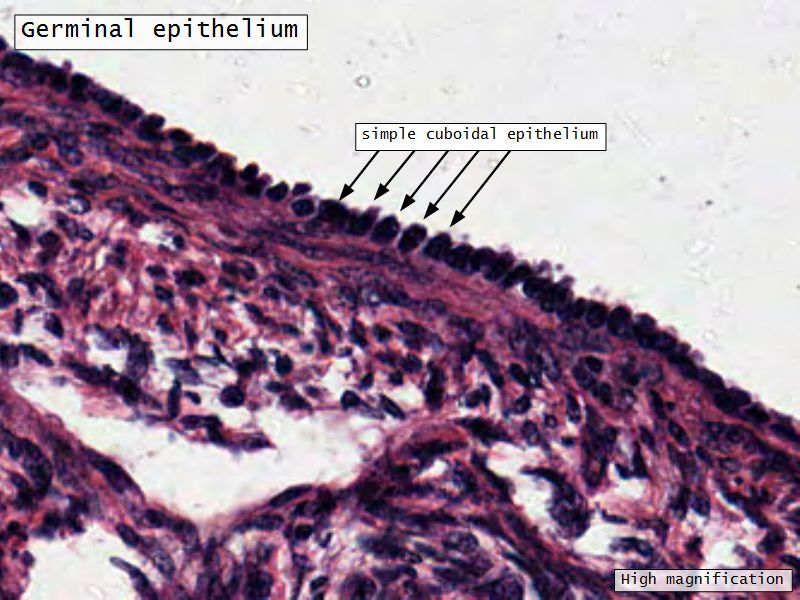

Germinal epithelium

- Misnomer

- NOT source of primary follicles

- Cover capsule

- Simple squamous/cuboidal epithelium